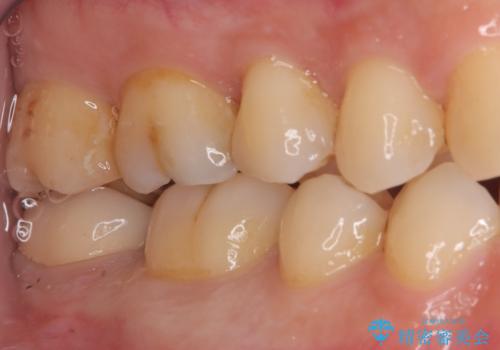

- 右下奥歯の詰め物が繰り返し欠けるとの主訴で来院されました。レントゲンとお口の中を詳細に診査した結果、以前の詰め物が咬み合わせの強い力に耐えきれず、また歯との適合も不十分であることが確認されました。患者様と相談し、今回は強度と耐久性に優れ、見た目も自然なセラミッククラウンで修復する治療計画を立案しました。これにより、再治療のリスクを減らし、長期的に安定した咬み合わせの回復を目指します。

治療では、まず古い詰め物を丁寧に取り除き、虫歯がないか確認しながら歯を丁寧に形を整えました。その後、精密な型取りを行い、患者様の歯の色や形に合わせたオーダーメイドのセラミッククラウンを作製しました。セラミックは天然歯のような透明感があり、非常に審美性に優れています。また、金属を使用しないため、金属アレルギーの心配もありません。